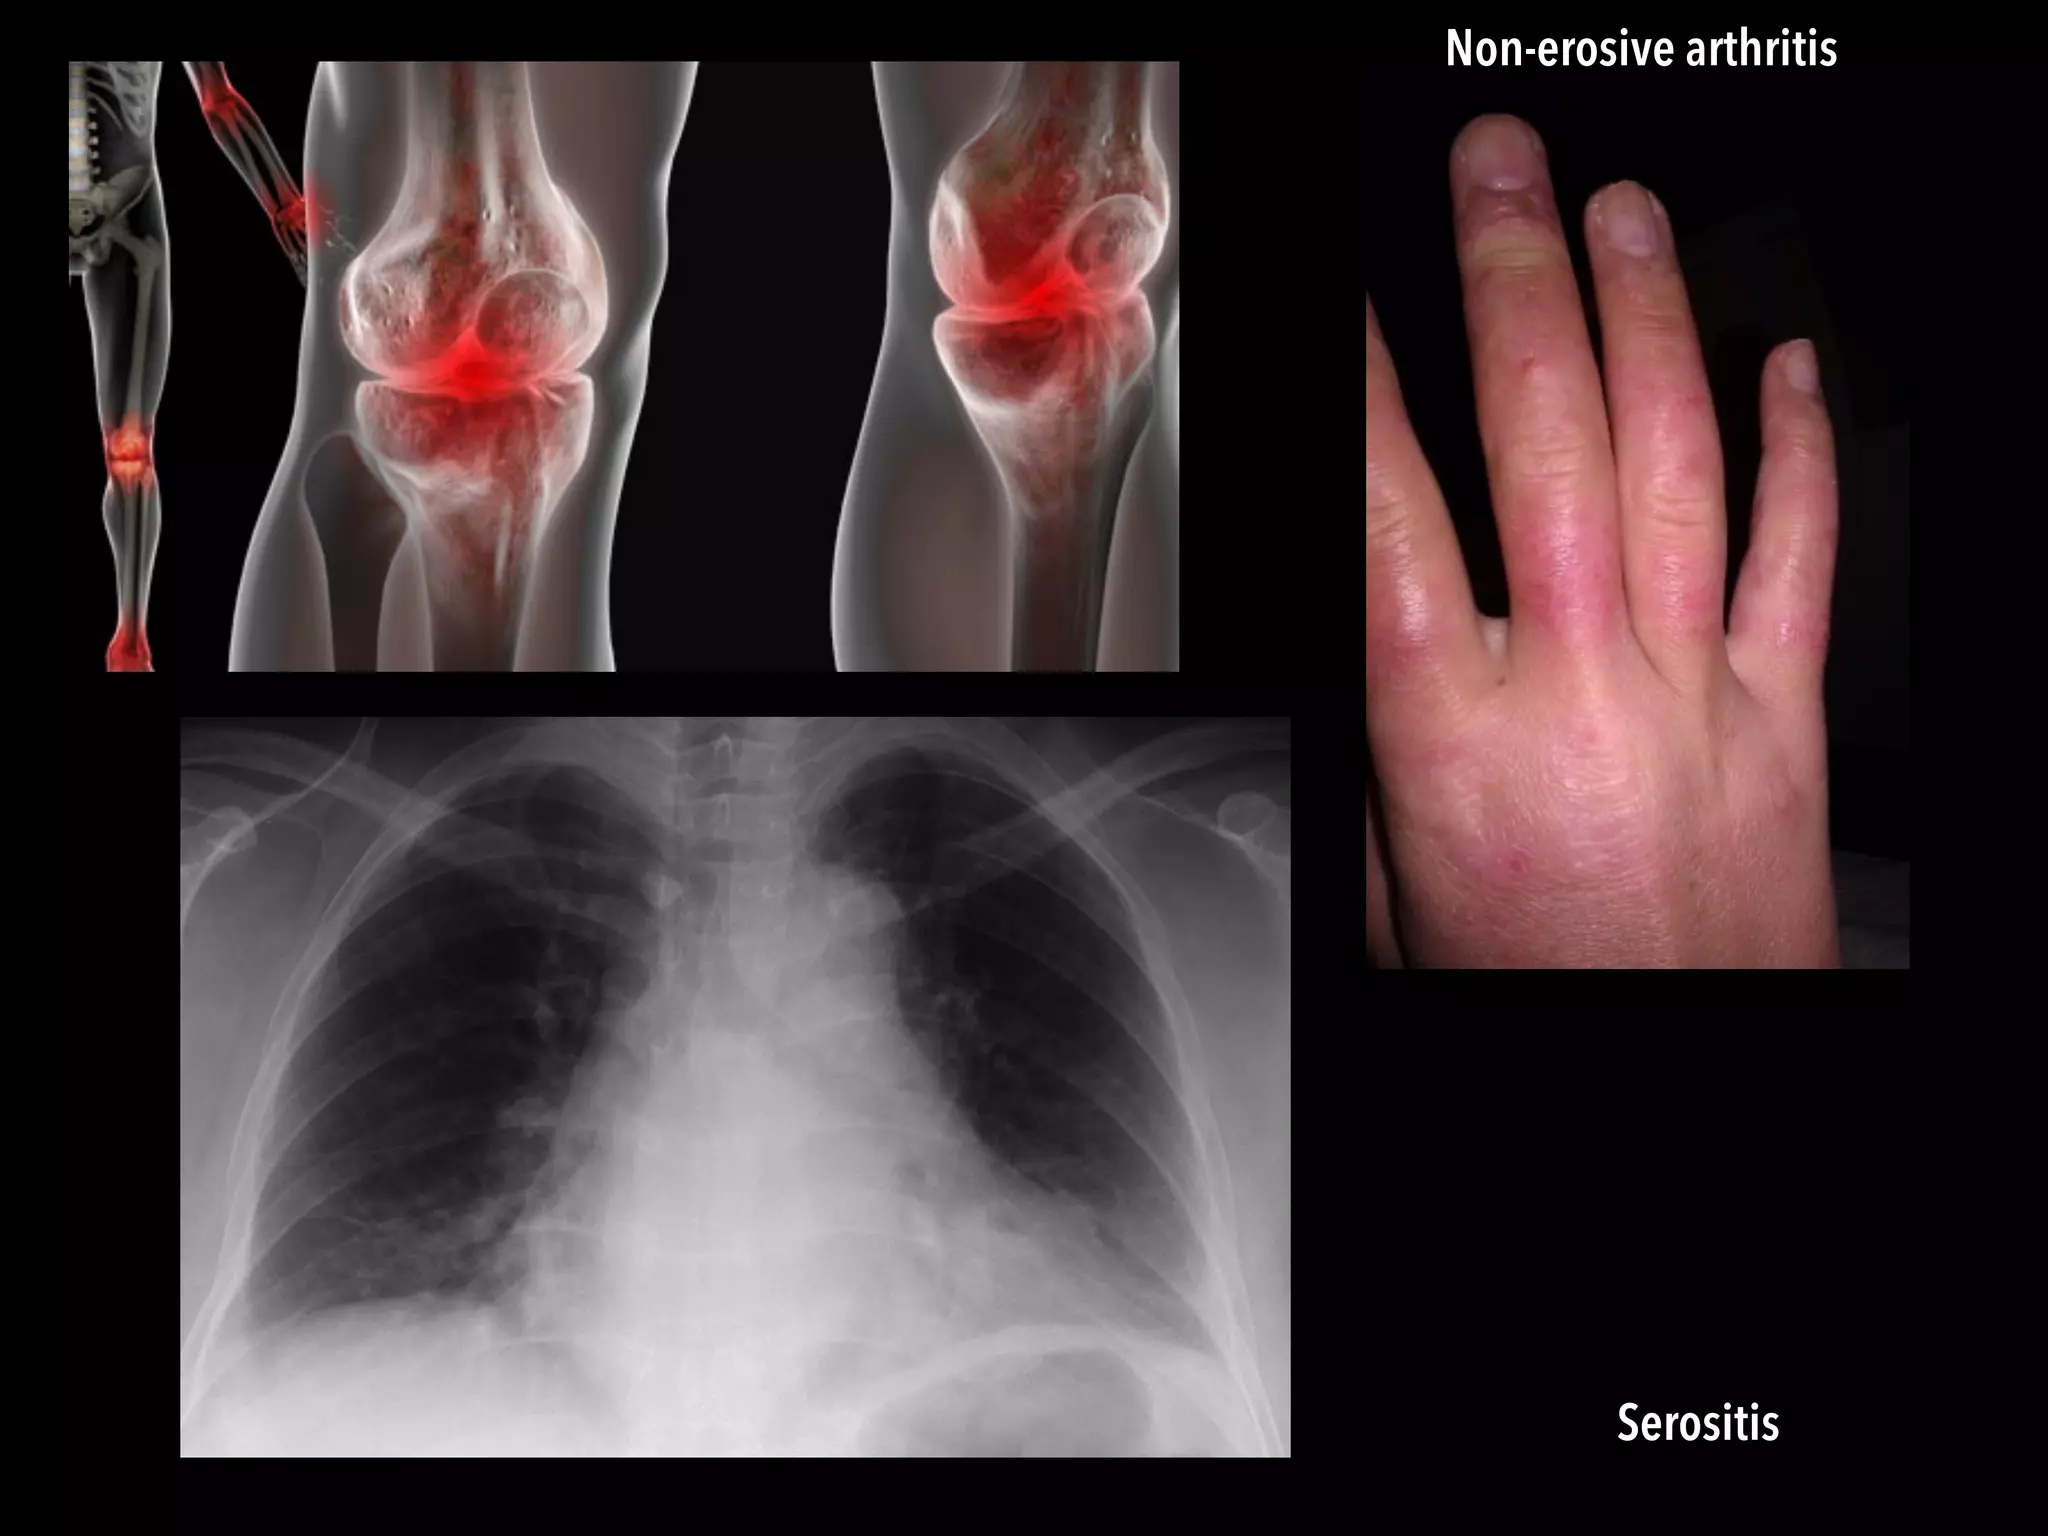

Serositis

Non-erosive arthritis